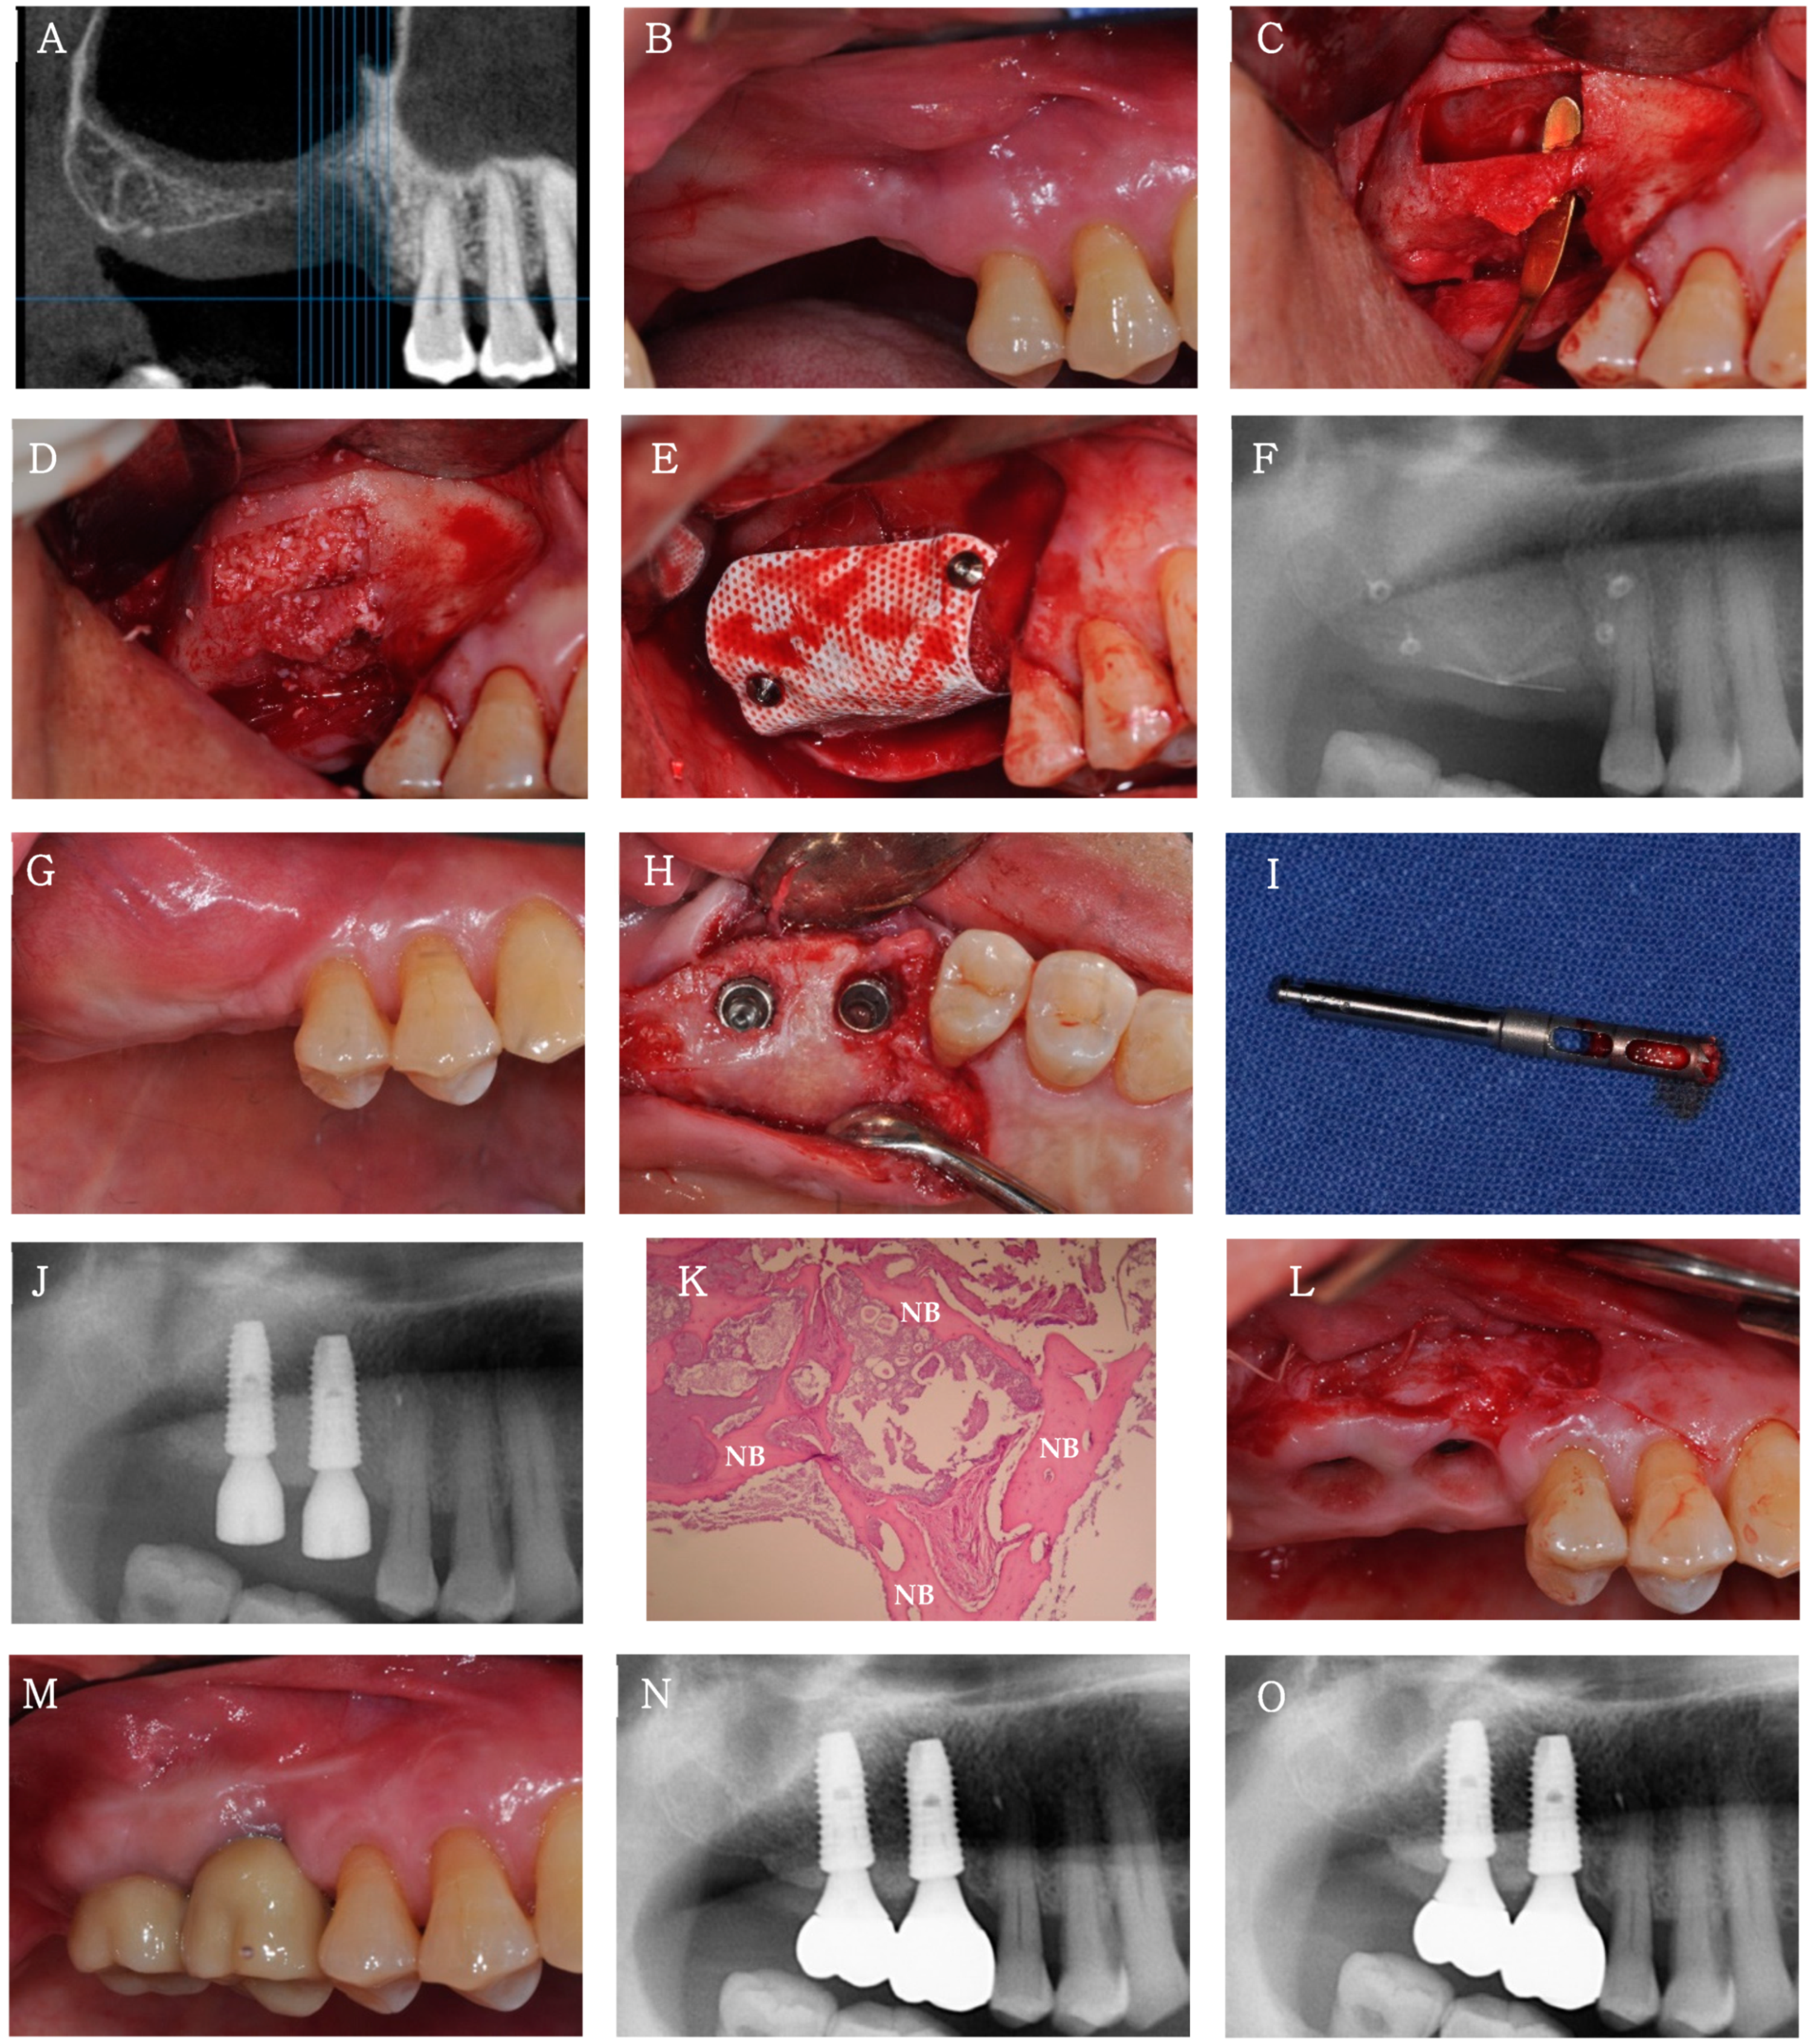

A 63 year old man visited the clinic for sinus augmentation and implant placement in the 16–17 region. Because oroantral communication (OAC) was expected on radiographic evaluation, vertical ridge augmentation with simultaneous sinus floor elevation was planned. After a piezoelectric lateral bony window osteotomy and sinus membrane elevation, sinus grafting was performed with a mixture of Bontree® and whole blood, followed by bony window replacement. Next, vertical ridge augmentation was performed with Bontree® mixed with whole blood and a titanium-reinforced d-PTFE membrane (Cytoplast® Ti-250, Osteogenics Biomedical, Lubbock, TX, USA). A single-stage implant surgery for 16 and 17 was planned 6 months postoperatively, because the radiograph showed sufficient hard tissue volume in the 16–17 region, indicating the resolution of OAC. A core biopsy was conducted before drilling at site 16 for implant placement. The biopsy was harvested through the alveolar process at a depth of 10 mm using a trephine bur with an inner diameter of 2 mm. High primary stability was obtained when the implants (Superline®, Dentium Co. Ltd., Seoul, Korea) for 16 and 17 were placed, and sufficient buccal and lingual marginal bone width was also confirmed. The harvested specimens were fixed using paraformaldehyde in 4% buffered saline, followed by demineralization. The specimens were processed into paraffin blocks, and a microtome was used for micro-sectioning. Next, hematoxylin and eosin staining was performed. Four months after implantation, modified periosteal fenestration [,,], which we first suggested as a free gingival graft alternative, followed by the application of an absorbable periodontal dressing, was performed because of the loss of attached mucosa buccally. The final prosthesis was inserted 6 months after the single-stage implant surgery (Figure 6).

Figure 6.

Clinical case 3. (A,B) Clinical and radiographic views before alveolar ridge and sinus augmentation in the 16 and 17 regions. (C) Buccal view after a piezoelectric bony window osteotomy and sinus membrane elevation. An oroantral communication is seen. (D) Sinus graft with Bontree®. (E) Vertical ridge augmentation with Bontree® and titanium-reinforced d-PTFE membrane after the replacement of the bony window. (F) Radiograph after sinus and ridge augmentation. (G) Buccal view before placement of implants 16 and 17, 6 months after sinus and ridge augmentation. A coronally positioned mucogingival junction line is observed. (H) Occlusal view of implants 16 and 17 immediately after placement. (I) The core biopsy in the 16 region using a trephine bur. (J) Radiograph after the single-stage implant surgery. (K) Histological examination. New bone formation (NB) is observed with no inflammatory tissue (H&E-stained; original magnification × 100). (L) Buccal view after performing a modified periosteal fenestration 4 months after the single-stage implant surgery. (M,N) Clinical and radiographic views of the final prosthesis 6 months after the single-stage implant surgery. (O) Radiograph at 1 year after loading.

A total of eight implants were placed in three patients who underwent sinus or alveolar ridge bone grafting with Bontree®. None of the patients had postoperative complications other than slight swelling at the surgical site. At 4 months after implantation, the ISQ values were >60 for all implants, indicating good implant stability (Table 1). All eight implants in all three patients were followed up for at least 12 months after functional loading, and the success rate, which was evaluated on the basis of the International Congress of Oral Implantologists Pisa Consensus implant health scale [], was 100% (Table 1). The radiograph at the 1 year follow-up showed integration of the implant with the regenerated bone and no bone loss or peri-implant radiolucency. No decrease in graft height was observed on any radiograph, and healthy peri-implant mucosa was established around all implants during the 1 year loading period.

3.2.3. Histological Findings

Histological analysis at the site of 16 in case 3, where sinus and ridge grafting was performed with Bontree®, revealed the deposition of newly formed bone around the residual synthetic bone graft and satisfactory incorporation of the newly formed bone with the residual synthetic bone graft. No foreign body reactions or inflammatory signs were detected (Figure 6K).